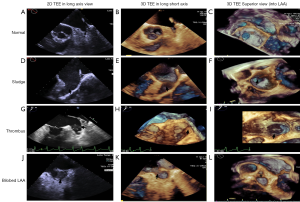

SEC, thrombus and relationship with LAA morphological typing in AFib patients

RT-3D TEE could detect LAA SEC and sludge visually. We defined four grades according to the severity SEC by 3D TEE. Four (3.6%) patients in the paroxysmal AFib group had mild SEC; no severe SEC was detected in these patients. However, there were 28 (13.3%) patients with LAA SEC grades 3–4, and 19 (9.1%) patients with LAA SEC grades 1–2 in the long-standing AFib group, and the differences were statistically significant (P<0.001). With regards to LAA thrombus clot, we evaluated the 2D TEE and 3D TEE in the LAA long axis view, and 3D TEE in the superior view into LAA, in all patients (Figure 5). Most paroxysmal AFib patients had normal LAA morphology and no SEC or thrombi (Figure 5A,B,C). SEC was definitely more likely to occur in the long-standing AFib patients (Figure 5D,E,F,G,H,I). In addition, the long-standing AFib group had a much higher thrombus occurrence rate, and thrombi were found in 22 (11.5%) patients compared with 2 (1.8%) in the paroxysmal AFib group (P<0.001). Moreover, with regard to diagnosis rate, 2D TEE mistook the acoustic artifact from crest (used for lobulation) as SEC, and even thrombus, in some cases (Figure 5J,K,L). The uncertainty of thrombi detection was significantly decreased by 3D TEE compared with 2D TEE (P<0.001), and the certainty of thrombi detection by 3D TEE also decreased slightly (P=0.06). In our study cohort, the rate of thrombi and prior stroke/TIA was not very high [24 (7.5%) and 29 (9.1%), respectively in the overall study population]. However, in most cases in our research, thrombi were more likely to occur in cauliflower type LAAs [odds ratio (OR) 2.1, 95% confidence interval (CI): 1.1–8.5, P=0.031].

In all AFib patients in our study, the certain thrombus diagnostic rate by 2D TEE was slightly higher than 3D TEE, and the uncertain thrombus diagnostic rate by 3D TEE dramatically decreased compared with 2D TEE. This is because in some particular situations, 2D TEE could not distinguish the pectinate muscles at the bottom of LAA from the small thrombus very well, whereas 3D TEE could easily distinguish them due to the highly-visualized surrounding and internal structure. RT-3D TEE could also clearly identify the surrounding structures, including the coumadin ridge, left upper pulmonary veins, coronary sinus, aortic and mitral valves, etc.